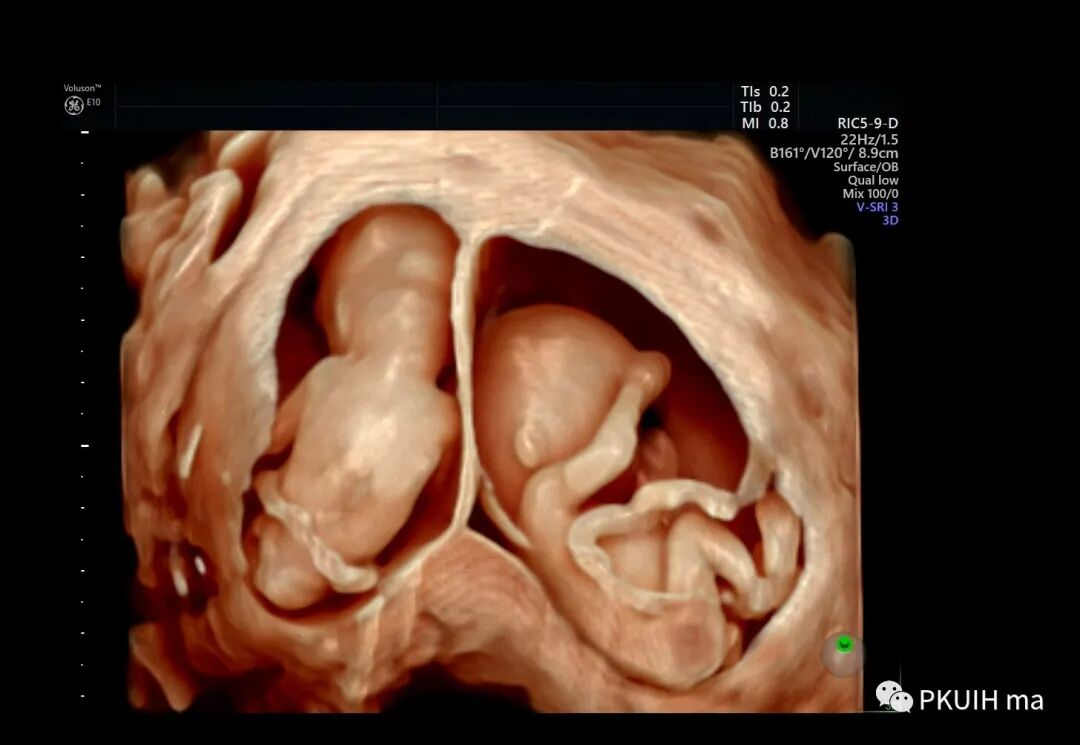

早孕双绒双羊双胎三维